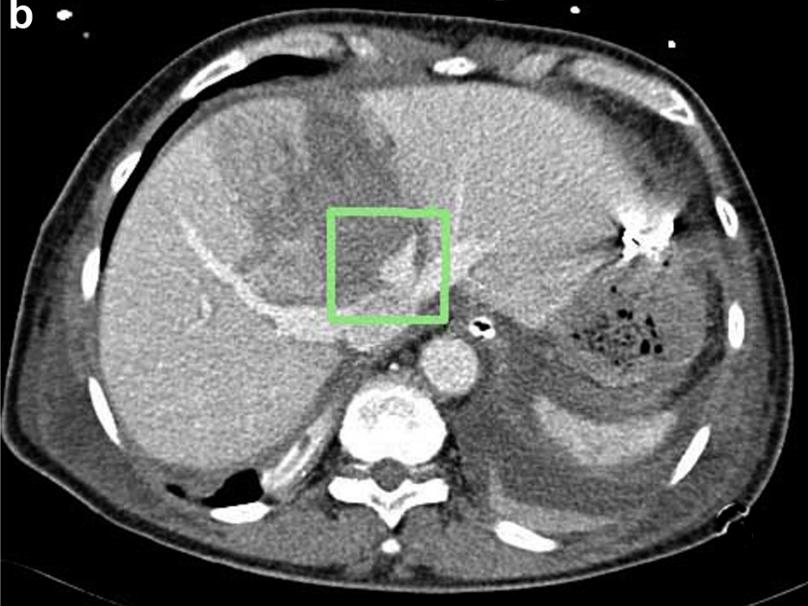

5.1. 肝损伤在CT扫描中诊断,从1级到IV级损伤,生命体征稳定,同时:a)损伤未累及肝门。b)肝周血肿比较局限。

- Liver injury diagnosed on CT scan with normalizing vital signs Grade I to IV: a) Injury not into hilum.b) Rim of blood fairly localized around liver.

肝脏损伤4度

肝脏损伤介入治疗

损伤部位标记